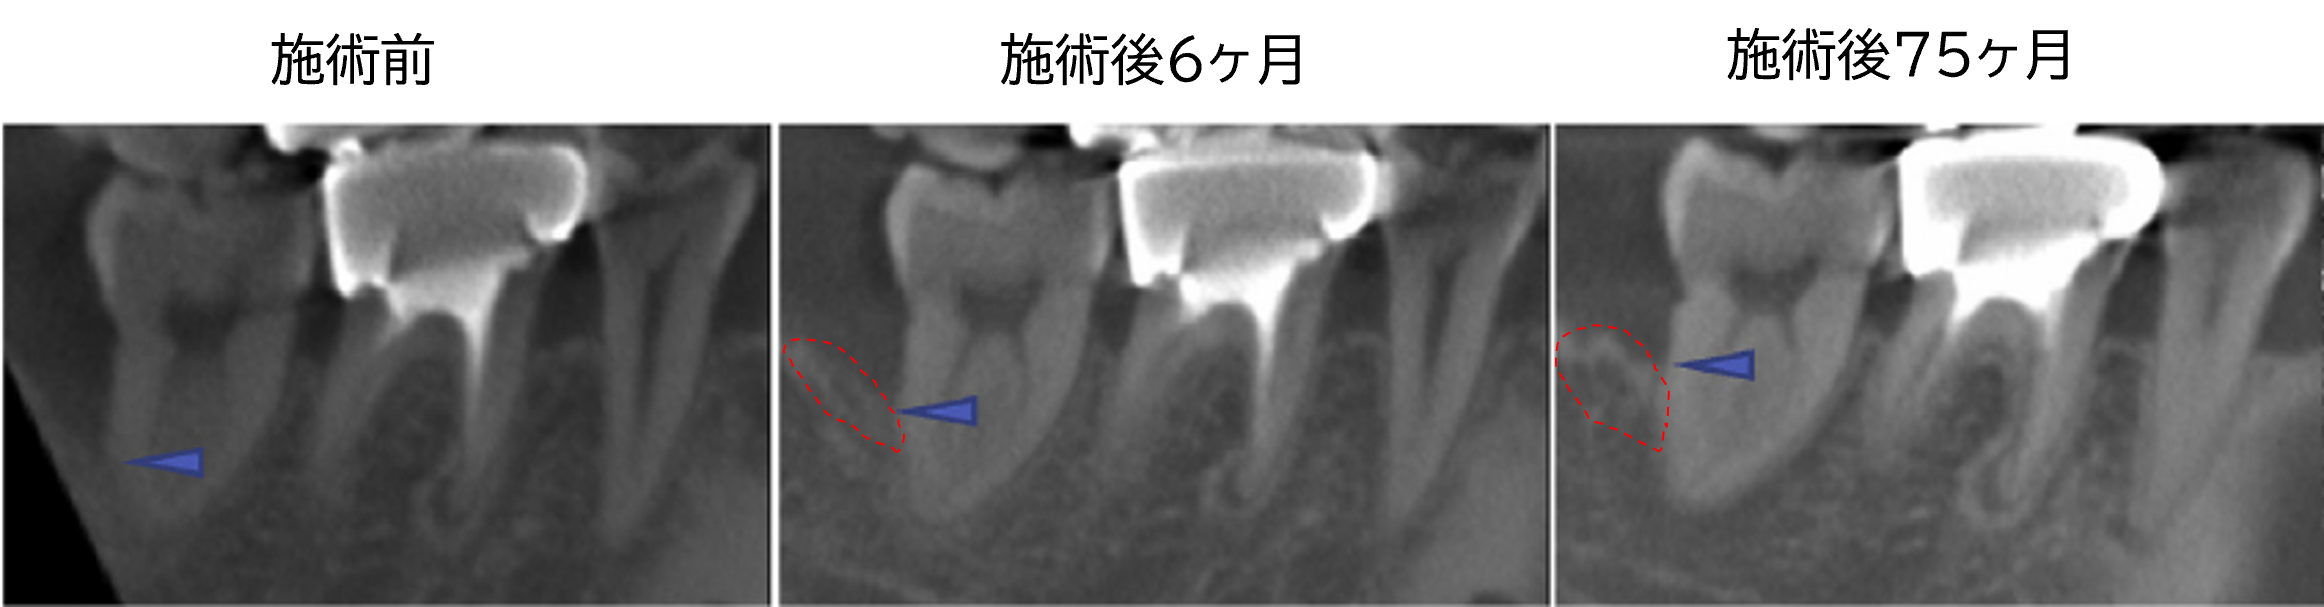

症例A|33歳男性

右下の第二大臼歯の奥側(遠心部)に、骨の壁が1面しか残っていない「1壁性骨欠損」が認められました。自己培養した歯根膜細胞シートを移植した結果、6ヶ月後には骨の高さが2.31mm増加し、その後も徐々に骨量が増える傾向が確認されました。

※矢印先端は骨欠損部の最遠心端を示す。

症例C|54歳男性

右下の第一大臼歯の頬側に、2面の骨が残る「2壁性骨欠損」が見られました。歯根膜細胞シートを移植したところ、6ヶ月後には骨の高さが4.6mm増加し、12ヶ月後にはさらに骨量が増加していることが確認されました。